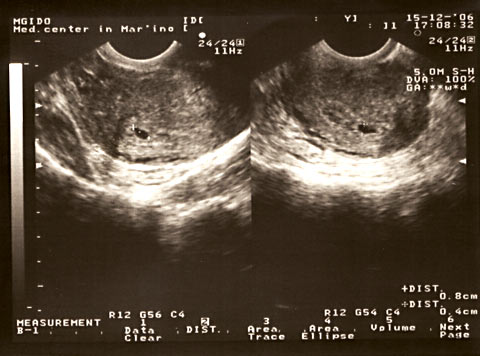

Preciso fazer um ultra-som?

No curso normal da gravidez, pode ser necessária uma ecografia na terceira semana obstétrica para confirmar a ovulação completa. Três semanas após a concepção, a digitalização durante a gravidez normal será quase ininformativa. O embrião parecerá um pequeno ponto no fundo da cavidade uterina.

Mas, com a suspeita de uma gravidez ectópica, é precisamente pelos resultados do ultrassom que o local de fixação do embrião ficará claro e será tomada uma decisão sobre novas ações. Para maior confiabilidade, o ultrassom pode ser realizado de forma transvaginal, ou seja, através da vagina. O procedimento é realizado com cuidado, cuidado e não causa desconforto.